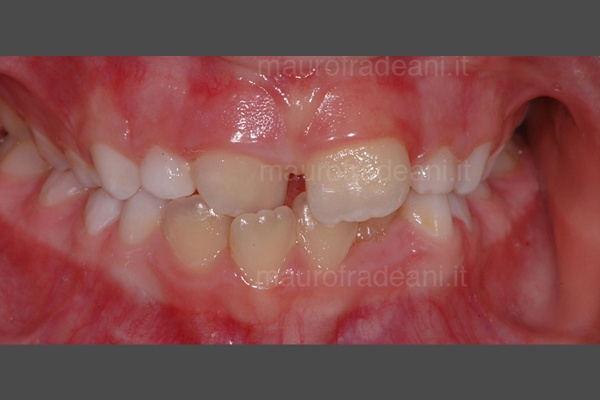

Early orthodontics: malocclusion and tooth crowding

1/6: Initial picture taken before early orthodontic treatment. The young patient presents a first class malocclusion with misalignment and dental crowding in both arches. The upper right central incisor is in reverse bite with the lower one.

4/6: The right lateral view shows the backward position of the upper right central incisor, which determines the incorrect occlusion with the lower arch.

5/6: Right lateral view picture showing the correct position of the upper right central incisor at the end of the orthodontic treatment.

6/6: Front view at the end of the orthodontic treatment: both the misalignment and the initial dental crowding have been fixed.